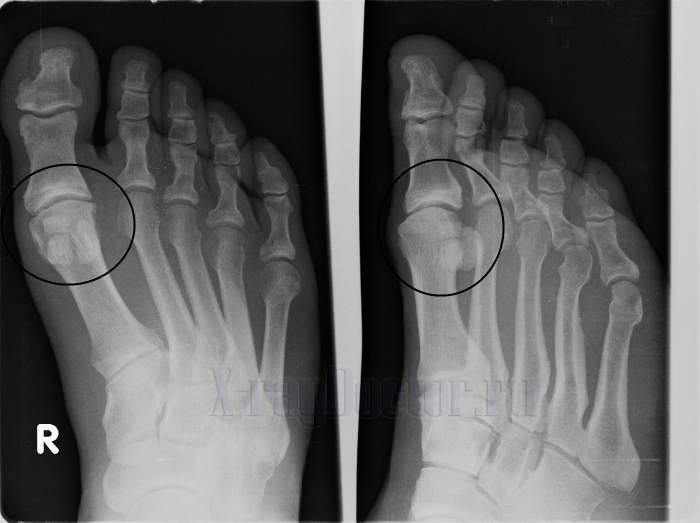

Рентгеновский снимок артроза стопы

Протокол описания: На представленной рентгенограмме стопы визуализируется сужение суставной щели 1-го плюснефалангового сустава 1-го